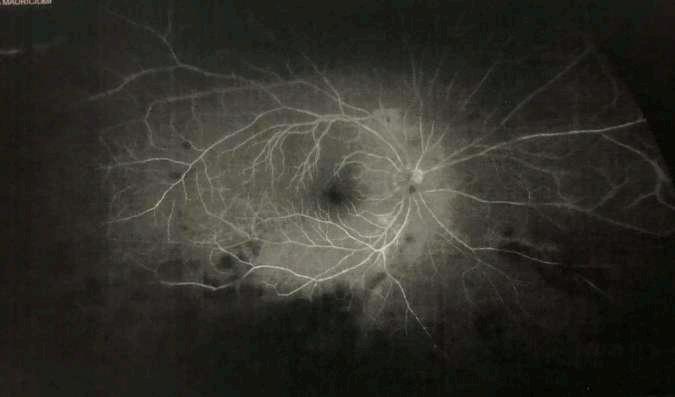

A la angiografía con fluoresceína (Fase activa)

ü Las áreas perfundidas demuestran una hiperfluorescencia en tiempos venosos con fuga tardía tanto a nivel tisular como vascular.

ü Las áreas isquémicas presentan una hipofluorescencia precoz con hiperfluorescencia por impregnación escleral tardía.

Clement F “Angiografía” Diagnóstico por la imagen en la retina, Sociedad Española de Retina y Vítreo, editado por Ignasi Jügens, Elservier, 2014, pp 41-66 A

Fase arterial

Fase A-V (arterio-venosa) Fase venosa

B C